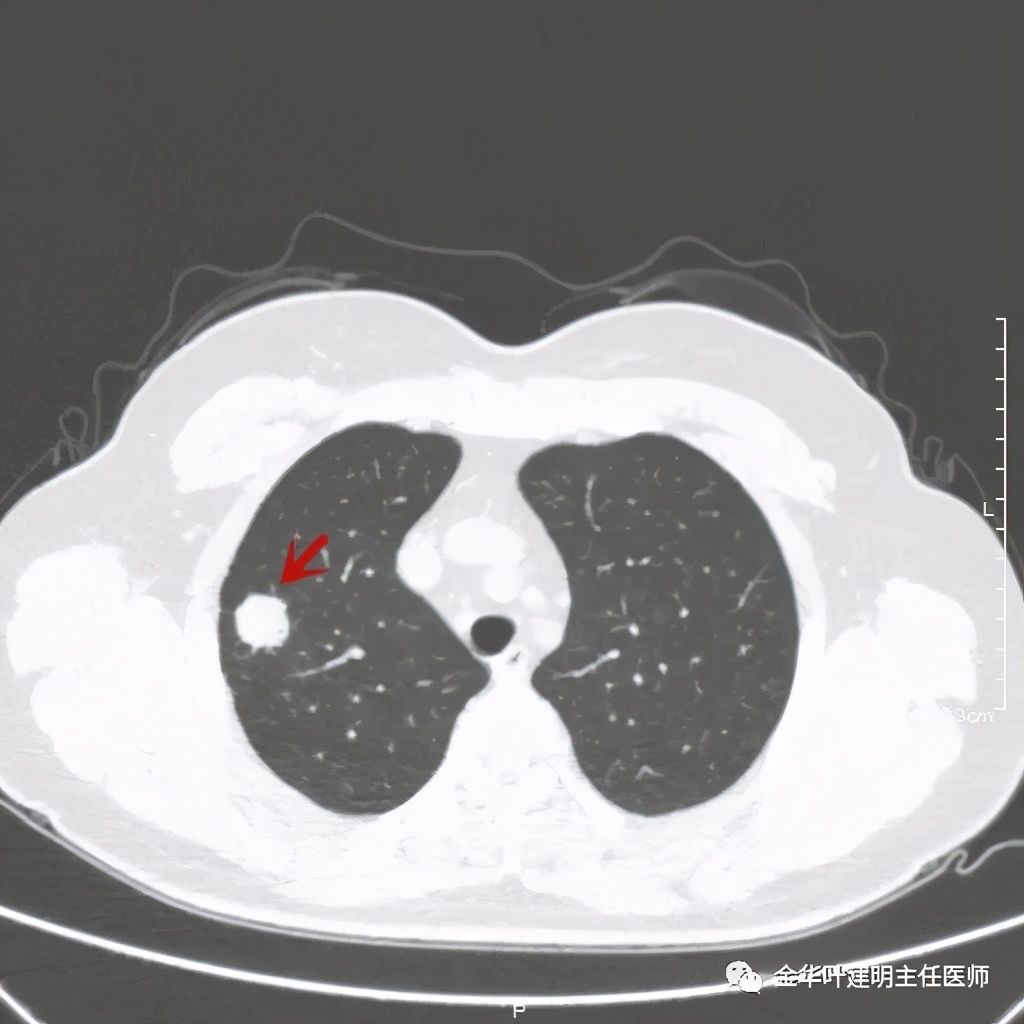

主病灶非常光滑

上图同样示与胸膜近,但无牵拉

总体感觉病灶较大,但边缘过于光滑,缺乏收缩力,没有毛刺征、分叶征、胸膜凹陷征;旁边却有多发微小实性或似磨玻璃结节,周围不清爽。让人感觉非肿瘤性质,炎性可能性大些,比如结核等。那么纵隔窗又是如何呢?我们选两个层面来看: